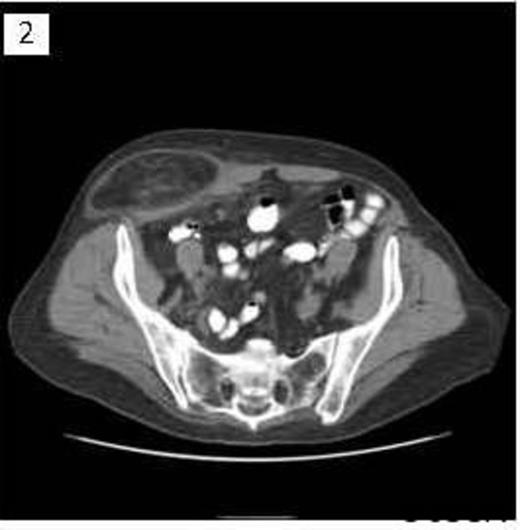

A 68 year old female presented to clinic with a several year history of right lower quadrant abdominal discomfort and “bulge”. Physical exam demonstrated a reducible mass originating in the inguinal region that tracked cephalad above the level of the inguinal ligament. CT imaging revealed a large inguinal hernia defect (Figure 1) with herniated bowel coursing 13cm cephalad between the external and internal abdominal oblique muscles (Figure 2 & 3).